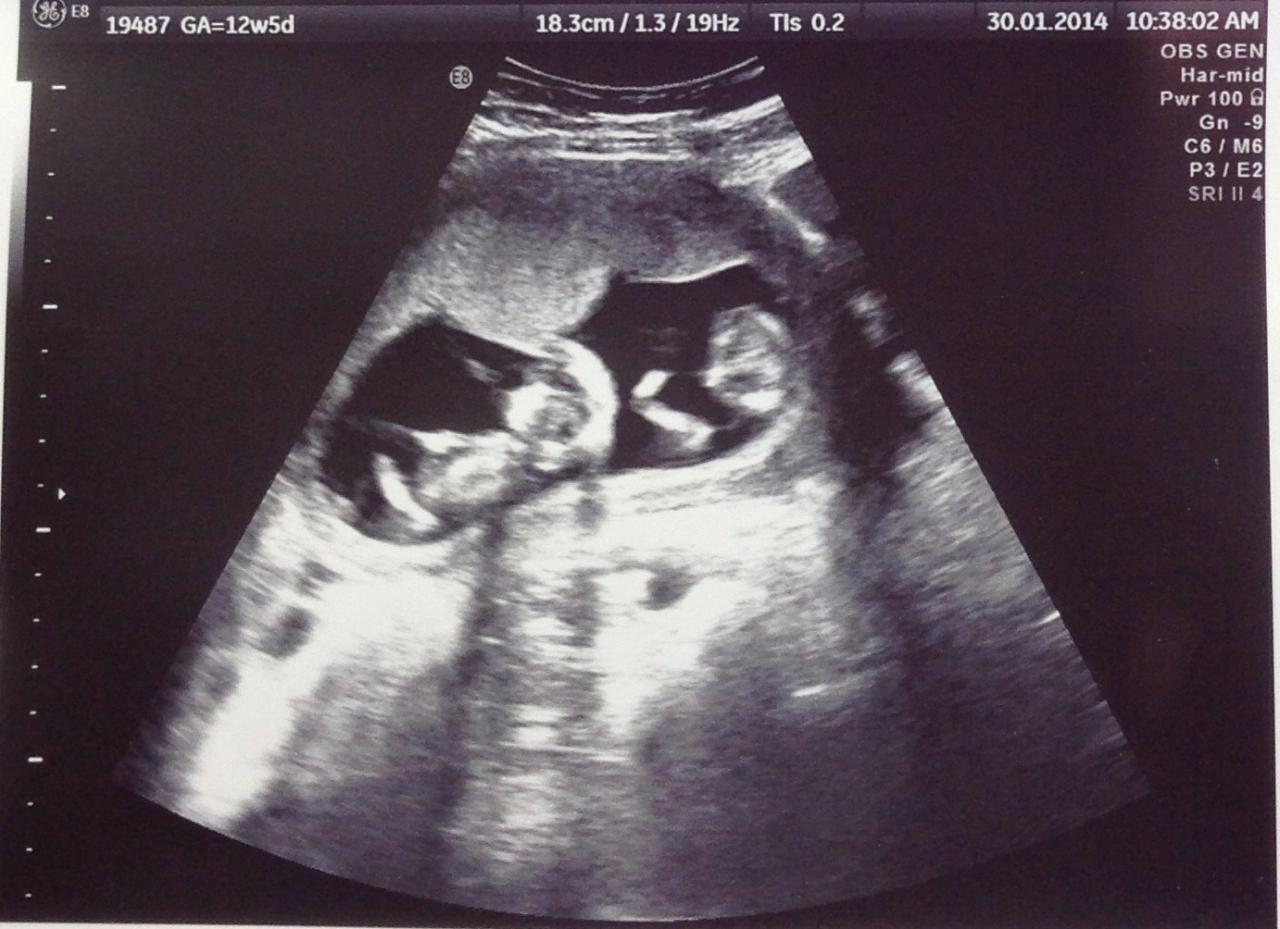

توائم

جينات الرجل أم المرأة .. من يتحكم في فرص الحمل بتوائم؟